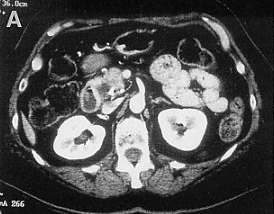

Developing a scoring system for staging patients with hepatic colorectal metastases is important for prognosis and for identifying those who will benefit from additional systemic therapy.

Due to advances in chemotherapy, biologic therapy, and the development of liver-oriented treatment options, the survival of patients with metastatic cancer has more than doubled, and increasing numbers of patients have been cured, even among those with advanced disease.

This article will review the current practice of hepatic resection for colorectal liver metastases, including the possibility of combined resection of hepatic metastases at the time of resection of the primary cancer.